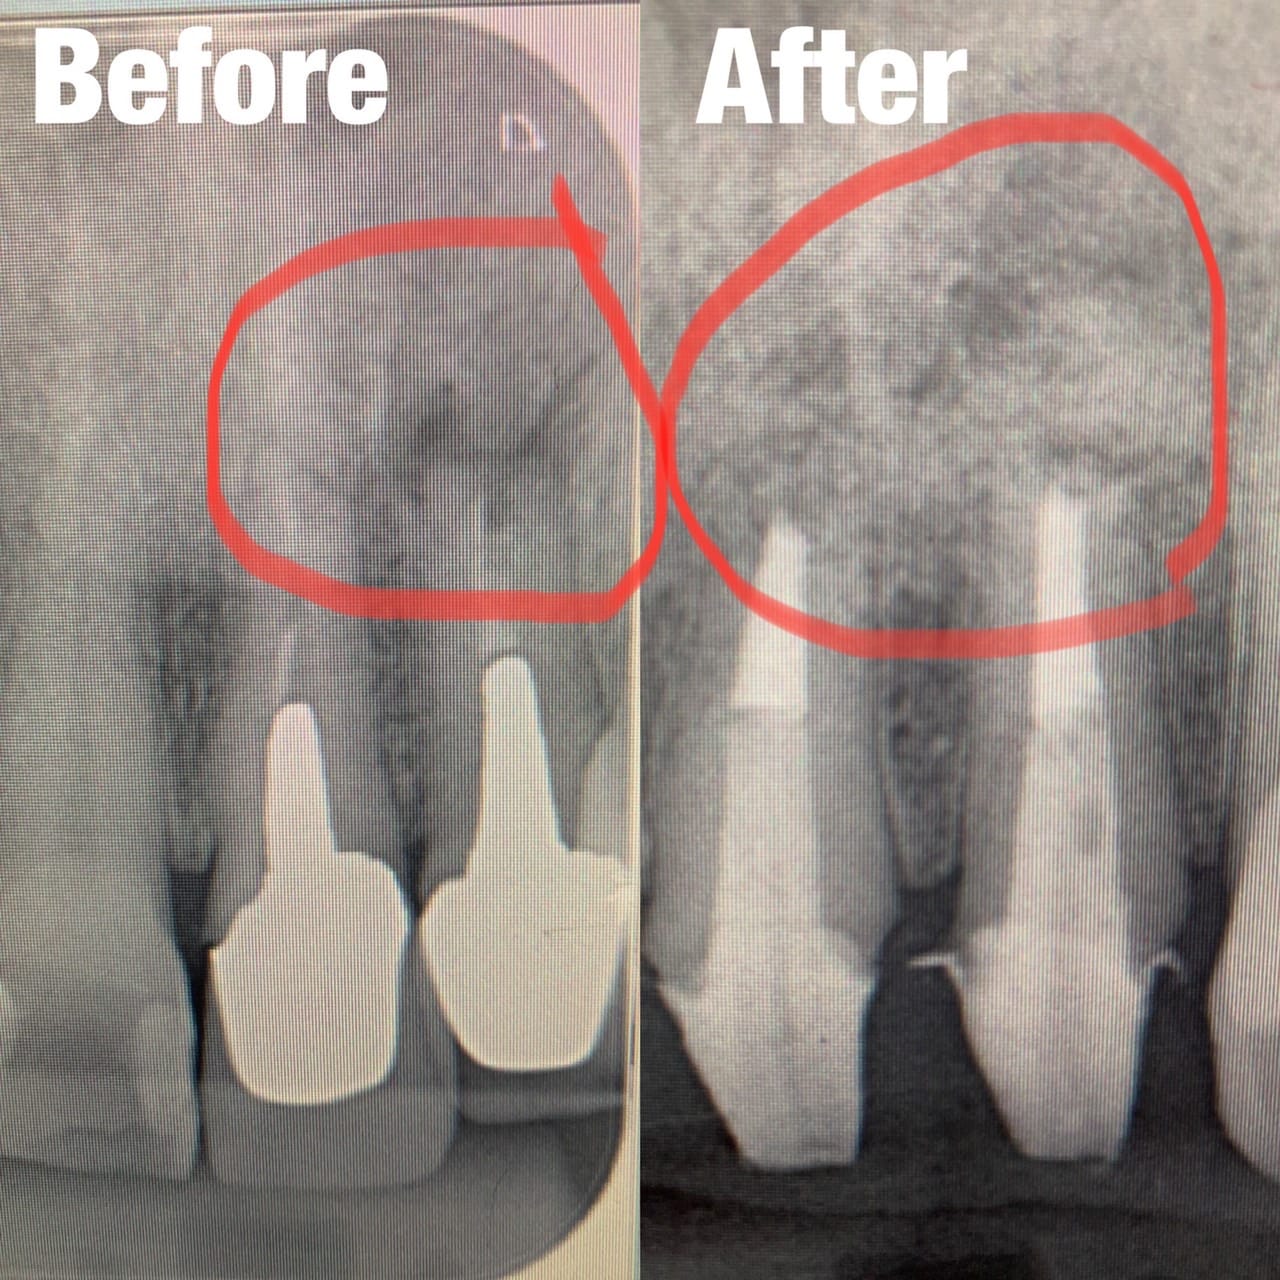

Case034

広島からの患者様です。

前歯を綺麗にしたい。インプラントをしたい。

という主訴で東京の歯医者をいろいろ調べて当院を選んでくださいました。

毎回、遠い中しっかり通ってくださり、選んで頂けた嬉しさと、その気持ちに応えたいという想いで診療させて頂きました。

前歯はご希望のお色でラミネートベニアでは出せない透明感のあるセラミックに上下左側7はインプラントをさせて頂きました。

左上は破折で温存不可。

骨も少なかったので、サイナスリフトも行い計五回の来院で被せ物を入れさせて頂きました。

左下は前回のクリニックでの埋入位置が深すぎて食べカスも毎回詰まる、セルフメンテナンスではら汚れも取れない。インプラント周囲炎にもなっていたので、一度前のインプラントを除去し、そこから新しくインプラントを埋入し、診療させて頂きました。

インプラント、歯並び、審美歯科にご興味のある方はいつでも相談にお越しください。

担当 理事長 佐藤 悠野